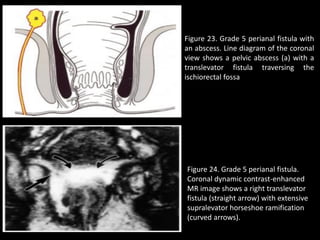

Grade 5:

• Grade 5: Supralevator and Translevator Disease.—

• In rare cases, perianal fistulous disease extends above the insertion

of the levator ani muscle.

• Suprasphincteric fistulas extend upward in the intersphincteric

plane and over the top of the levator ani to pierce downward

through the ischiorectal fossa.

• Extrasphincteric fistulas reflect extension of primary pelvic disease

down through the levator plate (Fig 23). These fistulas pose

problems for management because further assessment is needed

to detect pelvic sepsis. Coronal dynamic contrast-enhanced MR

imaging elegantly demonstrates breaches of the levator plate,

which is clearly shown in this plane. In some translevator fistulas,

horseshoe ramifications to the contralateral side may occur (Fig 24).

Figure 23. Grade 5 perianal fistula with

an abscess. Line diagram of the coronal

view shows a pelvic abscess (a) with a

translevator fistula traversing the

ischiorectal fossa

Figure 24. Grade 5 perianal fistula.

Coronal dynamic contrast-enhanced

MR image shows a right translevator

fistula (straight arrow) with extensive

supralevator horseshoe ramification

(curved arrows).

Figure 23. Grade5 perianal fistula with an abscess. Line diagram of the coronal view shows a pelvic abscess (a) with a translevator fistula traversing the ischiorectal fossa Figure 24. Grade 5 perianal fistula. Coronal dynamic contrast-enhanced MR image shows a right translevator fistula (straight arrow) with extensive supralevator horseshoe ramification (curved arrows).